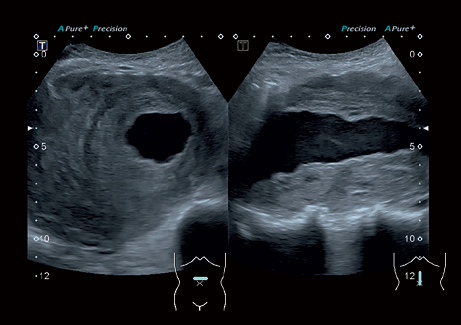

• Precision Imaging - технология получения изображений мелких деталей с четко очерченными границами и высокой однородностью

• MPR - функция мультипланарной реконструкции для визуализации исследуемой области в 3-х ортогональных плоскостях

• Трехмерная эхография в реальном времени с использованием специализированных 4D датчиков;